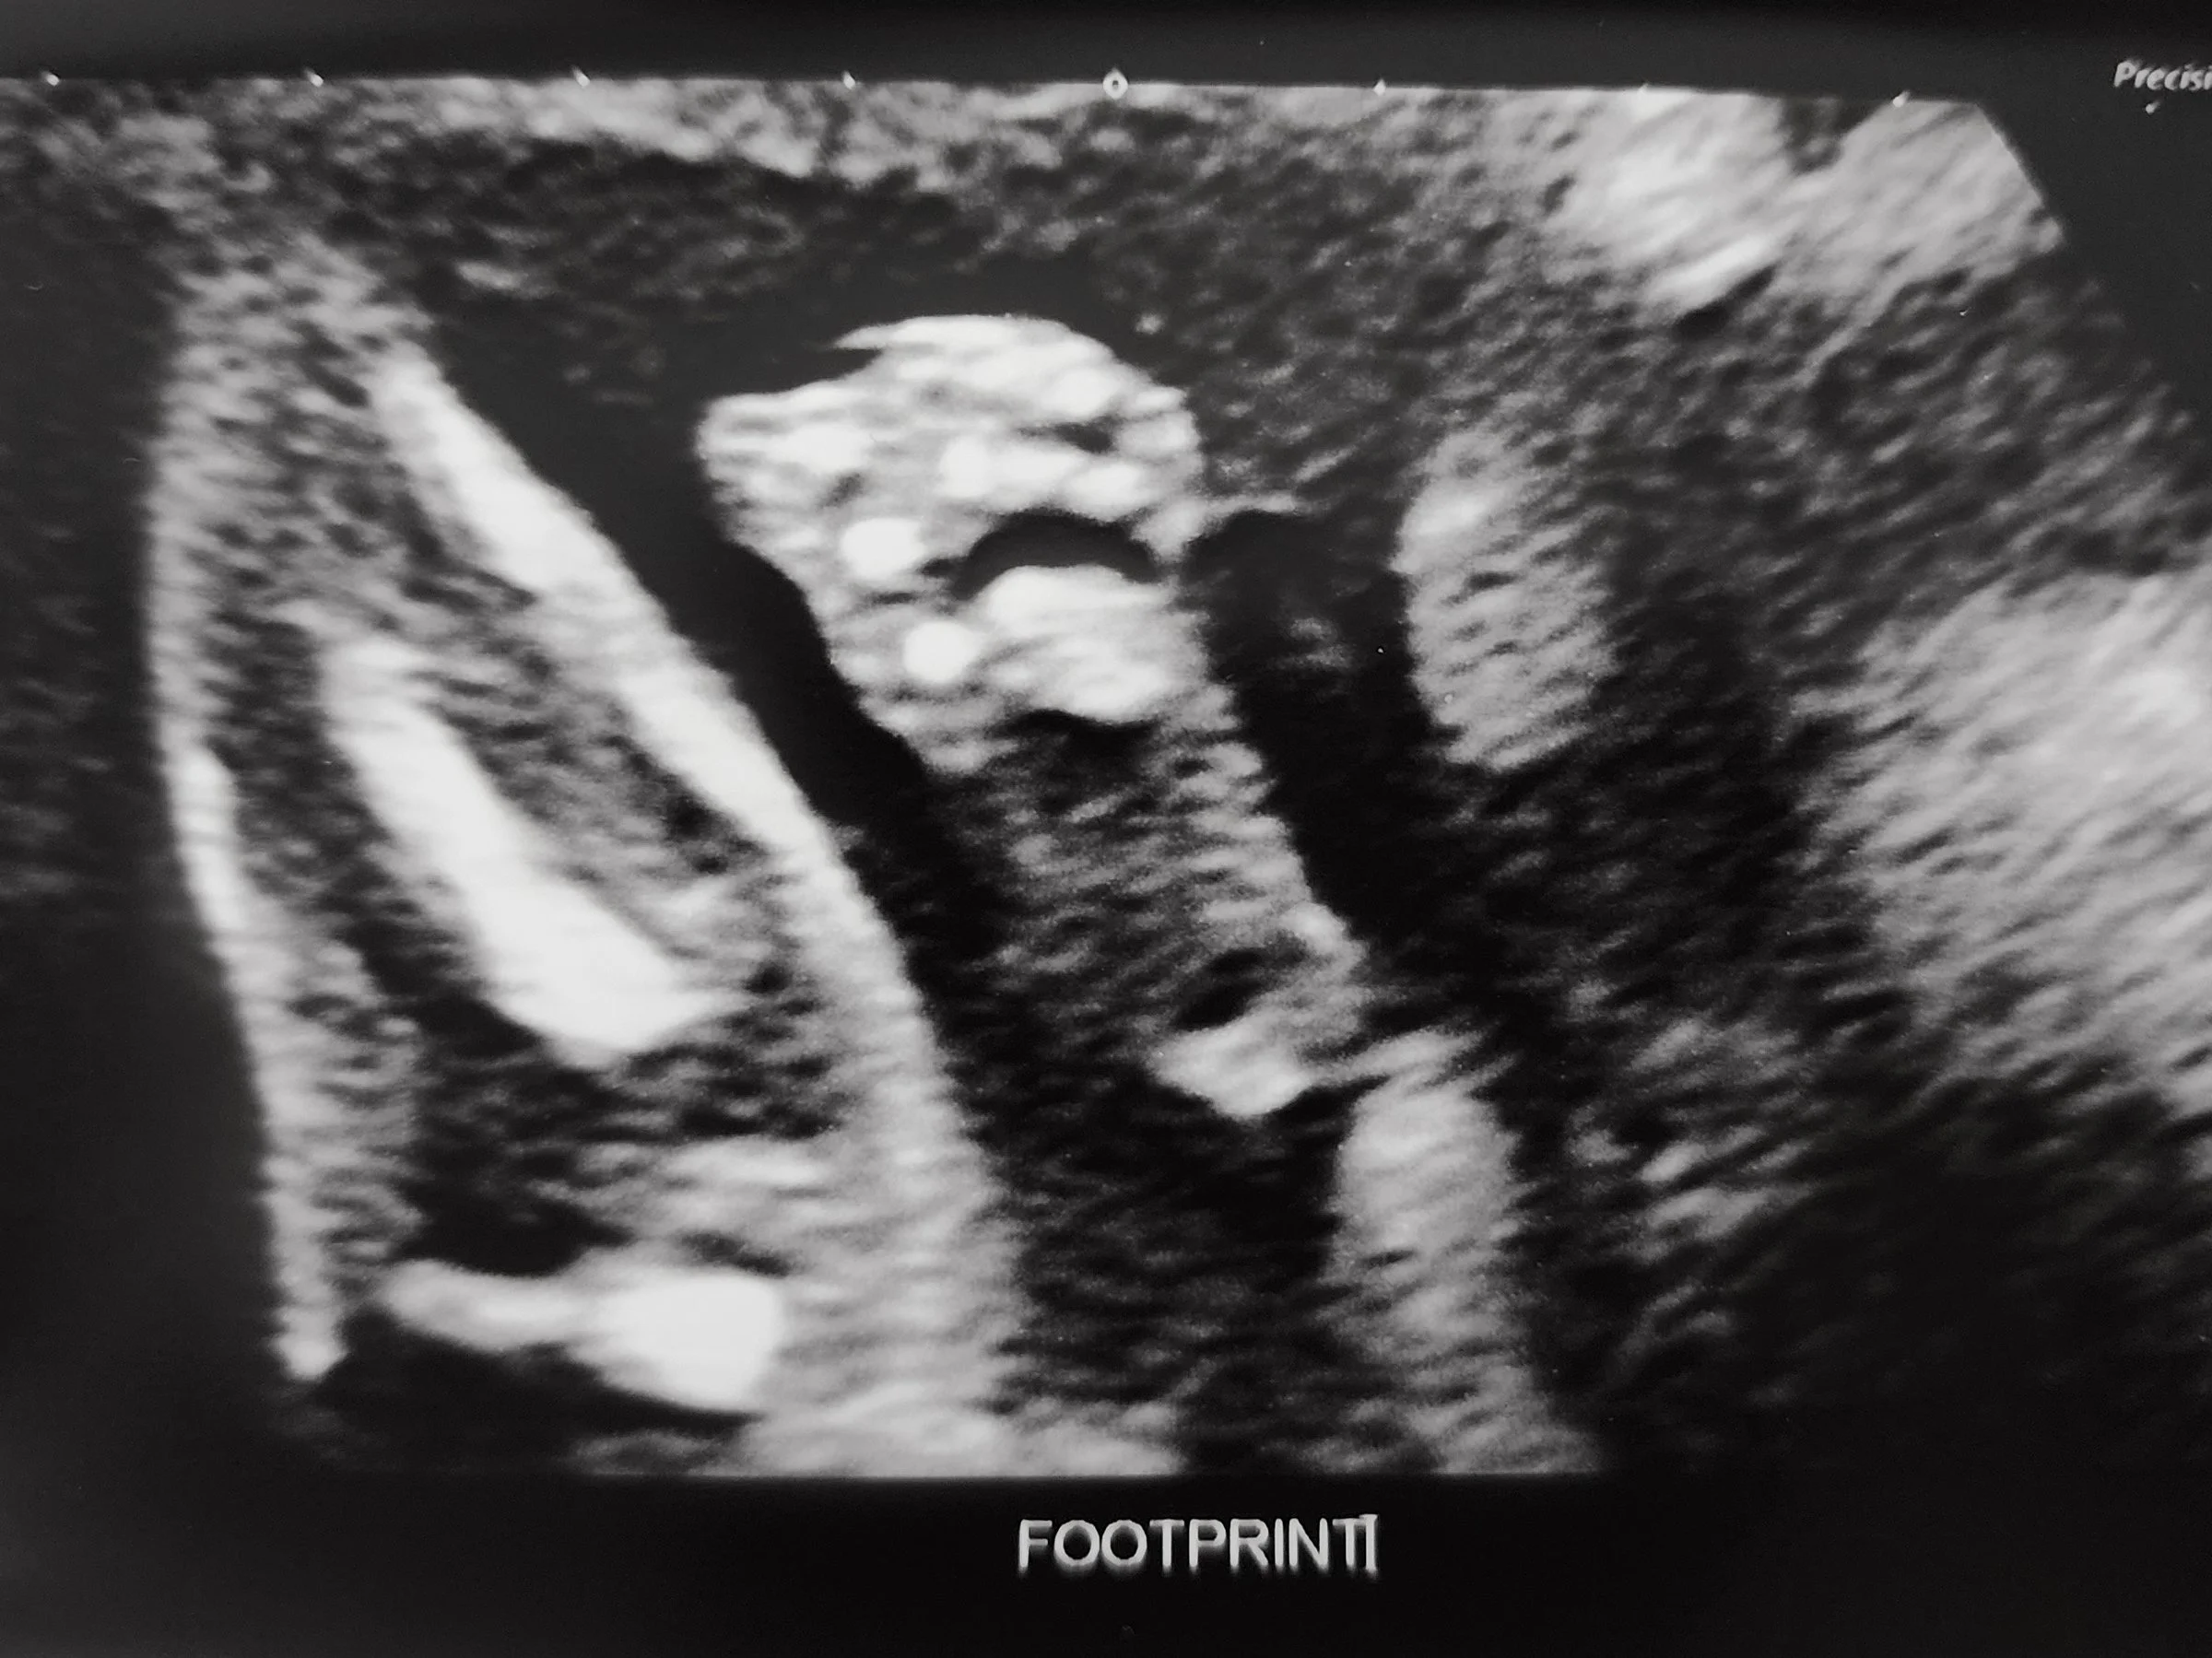

It was a busy summer for us this year! Whilst entering the second trimester and sharing the news with our family, we were also busy buying our first home! After years of being on the rental rollercoaster (aka having to move twice because owners wanted to sell - see here and here), we were finally in a decent place to take the leap into home ownership.

We spent a few weeks viewing different apartments but we had our hearts set on a specific location from the get-go. We found the apartment (2 bedroom + den) but took an extra weekend to rule out any other options. We made the final decision to put an offer in over lunch at Earls :) From initial inquiry to collecting the keys, the buying process was done within a couple of months. And within the next couple of months, we’ll be welcoming a new family here too!